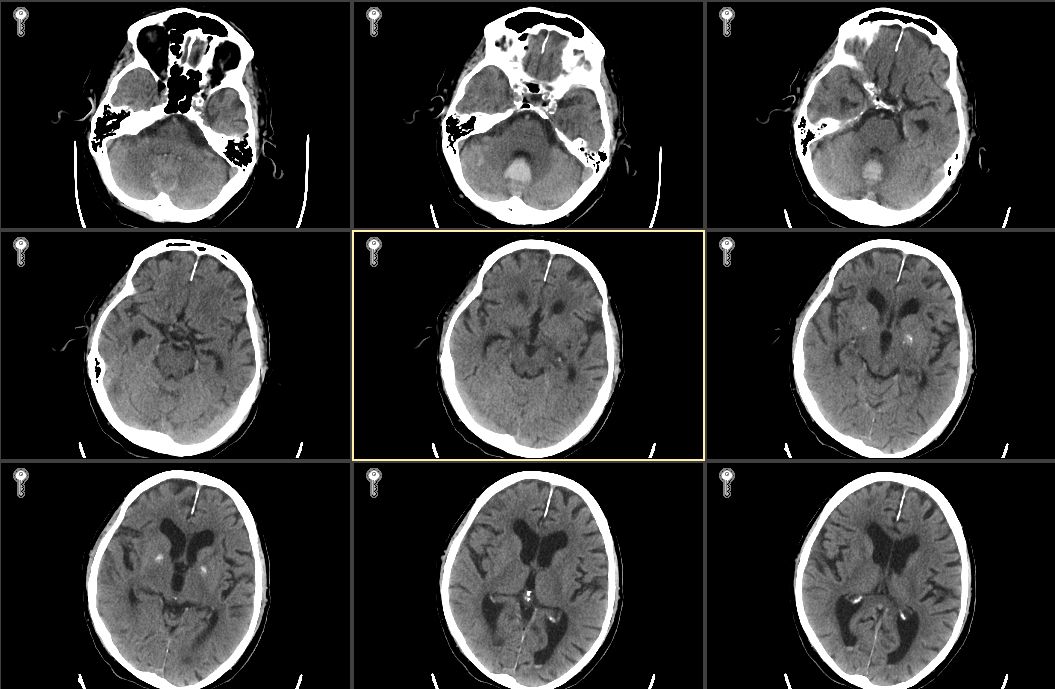

病例2,男性,80岁,因“突发右侧肢体无力1周,加重伴意识障碍1 d”由外院转入我院。外院头颅CT示左侧额颞叶片状低密度灶,诊断大面积脑梗死。头颅CTA示左侧颈内动脉及大脑中动脉部分闭塞,急诊溶栓治疗无效。既往有高血压病史20年,无冠心病房颤病史。入院查体:生命体征平稳,体温37.8 ℃,GCS 2-5-1,双瞳等大等圆,光敏,左侧肢体有不自主活动,右侧肢体无活动,右侧巴氏征阳性。入院诊断为左额颞大面脑梗,肺部感染,高血压病。入院后头肺CT见图 3。

| 图 3 入院患者头颅和肺CT |